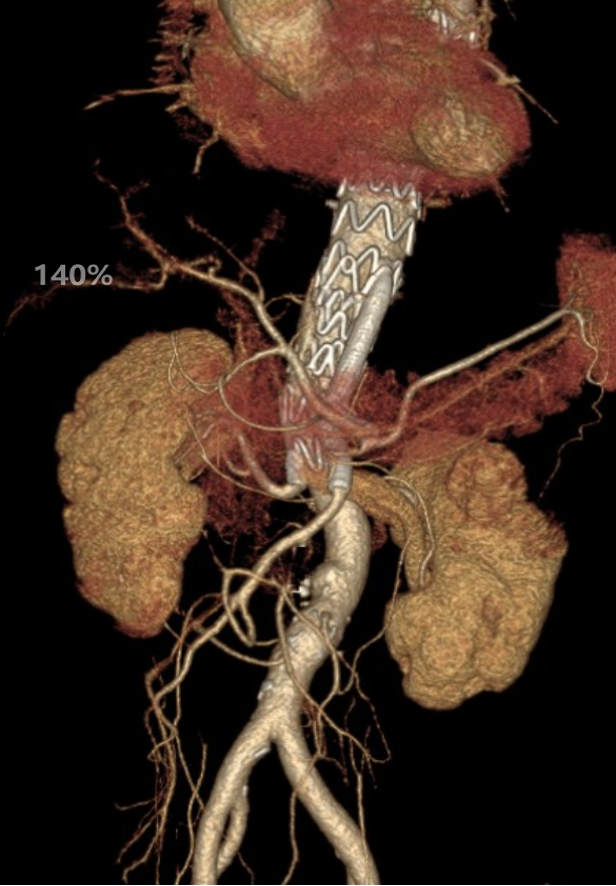

病例1 两开窗:

病例2 四开窗:

手术时间382分钟

造影剂用量320ml